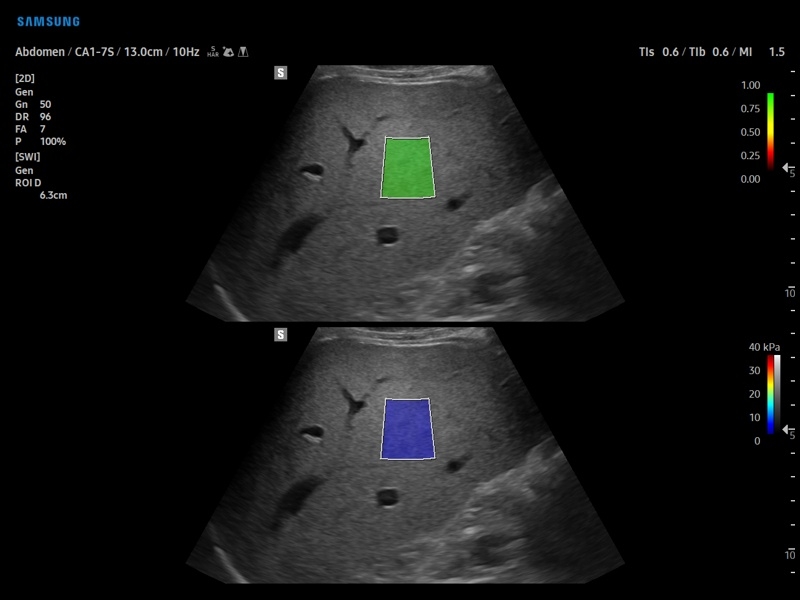

• S-Shearwave Imaging для эластографии сдвиговой волной

Компрессионная, Сдвиговая

Эластография сдвиговой волной/Эластометрия:

• Модуль S-Shearwave imaging – программа цветовой сдвиговой эластографии позволяющая автоматически определять индекс жесткости различных участков исследуемого объекта в кПа или м/с, получая при это еще и индекс достоверности данных RMI.